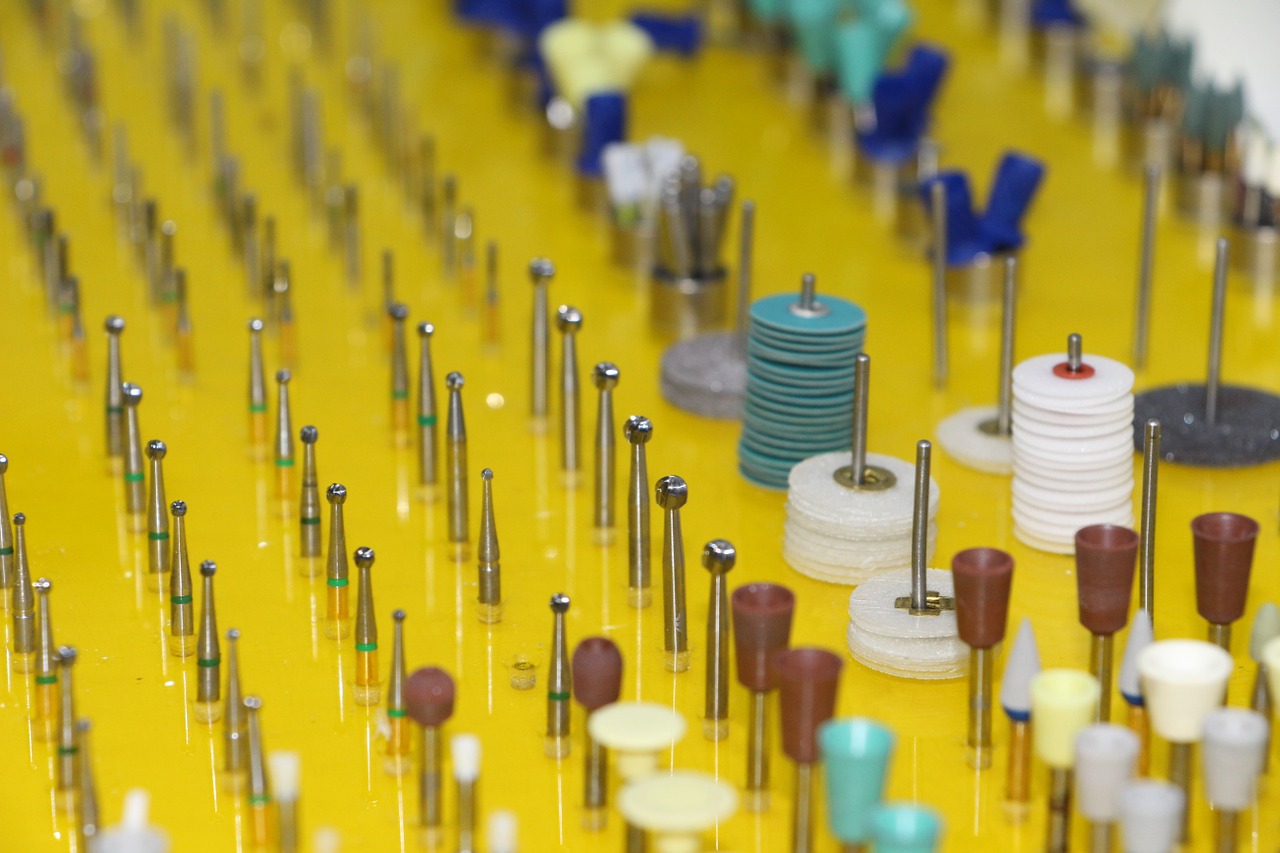

Stomatologia jest jedną z najlepiej rozwijających się gałęzi medycyny. Jeśli tylko się postaramy to nie …

Wiele osób nie zdaje sobie sprawy z tego, że zepsute zęby nie muszą już być …

Dbałość o zęby jest bardzo ważna. Niestety często po czasie okazuje się, że za mało …

Dbałość o zęby jest bardzo ważna. Niestety nierzadko po czasie ujawnia się, że za mało …

Zdrowe zęby, piękny uśmiech to powód do dumy. Dlatego że zęby towarzyszą nam przez całe …

Zły sposób odżywiania się, nadwyżka cukru mogą powodować pruchnicę, a w konsekwencji większe braki w …

Ładne białe zęby to marzenie wielu z nas. Nie tylko poprawiają wygląd ale sprawiają że …